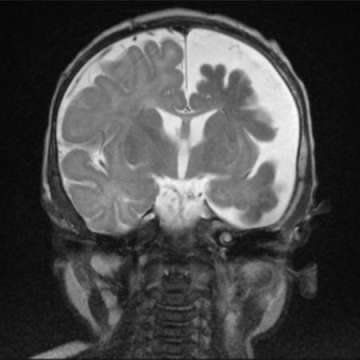

Neurologically, the infant or child may present with seizures that are progressively more difficult to control with medications. In addition, neurological deficits and developmental delay may result. Visual field defects may also occur with variable severity. Hydrocephalus (i.e. too much brain fluid) also may occur. A small proportion of patients have no neurologic abnormalities.

The reasons for neurologic progression in SWS are uncertain. One possible mechanism is the lack of blood flow and oxygen to the surrounding brain.